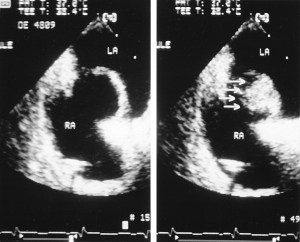

“You have an atrial septal aneurysm,” he said, (something I’d already been told over the phone), which also goes by its acronym, ASA. “It’s a bulge in the wall that separates the left and right atria of your heart, the two upper chambers. In your case, it bulges from the right side to the left, with every beat.” He drew a picture of it for me. (The ultrasound picture on top of this post shows an ASA, not mine, but similar — the labels RA and LA refer to the two atria, with the bulge in between.)

He leads me to darkened room with a computer and monitor. He offers me a rolling chair with no arms, beside his. Then he plays a short video, my echocardiogram from nine months ago. It’s a startling image, on a dark background with the outlines of the heart chambers in light colour, and everything in fast, jerky motion, like an animated GIF online, with whorls of colour that show blood flow.

“Here,” he points to the bottom of the screen. It takes some imagination, because the image is rotated 90 degrees, with the right side of my heart at the bottom. But then I see what he’s referring to, a sudden bulge with every heartbeat, where the straight septal wall stretches briefly sideways, into the left atrium, then returns to normal.

It’s hard to judge the size of the images because the whole video is enlarged, well beyond the size of a human heart, which is like a fist. It is alarming to watch, a weird, pulsating deformity. But Dr. Schwarz immediately reassures me.

“It’s not a remarkable ASA,” he says, “but it is unmistakeable.” (His language is always this precise.) He seems satisfied as he reviews the findings he wrote in his report on the test: “Aneurysm of the atrial septum with bulging towards the left atrium … could be a nidus for platelet aggregation and micro emboli” — in other words, the clots that caused my mini-strokes.

Having seen it with my own eyes, I tend to agree. I’d watched several similar videos of ASAs online, and mine resembles those. Back in his office, I ask why the second imaging technique delivered a contradictory conclusion to the first.

He explains: “The transthoracic echocardiogram is actually better for imaging the ASA, while the transesophageal echocardiogram is better for diagnosing a PFO.” (That’s the level of medical jargon you have to learn in order to understand a cardiologist!)